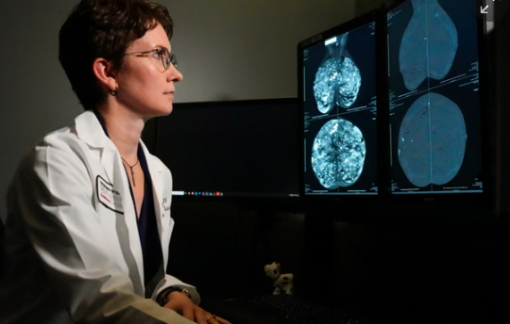

Một xét nghiệm bộ gen mới được đánh giá là bước đột phá trong điều trị ung thư vú sẽ giúp hàng triệu phụ nữ trên thế giới tránh được hóa trị.